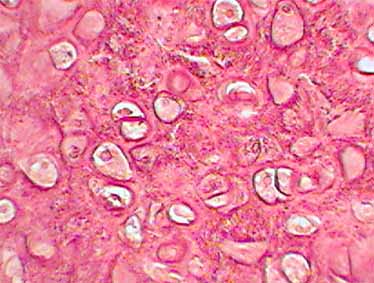

Hyaliner Knorpel

Hyaliner Knorpel ist mit Abstand die häufigste Knorpelart im menschlichen Körper - besonders während der Entwicklung.So bildet er das embryonale Skelett, das nachher durch Knochen ersetzt wird. Außerdem kommt es in der Nase, den Luftwegen (Kehlkopf, Luftröhre, Bronchien) und zur Unterfütterung von Gelenken vor. Durch die große Menge Wasser, die die Interzellularsubstanzen des hyalinen Knorpels (Proteoglykane, Hyluronsäure) binden können, hat diese Knorpelart druckelastische Eigenschaften, d.h. bei Druck verformt er sich bis u einem gewissen Grade, dann setzen aber die Abstoßungskräfte innerhalb der Interzellularsubstanz dem Vorgang einen gewissen Widerstand entgegen und sorgen auch dafür, dass wenn der Druck nachlässt, das Gewebe wieder in seine Ausgangslage zurückfindet. Hyaliner Knorpel ist die häufigste Knorpelart im menschlichen Körper.

Grundsätzlich besteht die extrazelluläre Matrix bei diesem Knorpel aus Grundsubstanz und Fasern. Die Fasern bestehen größtenteils aus Kollagen Typ II. Diese sind im Normalfalle im Lichtmikroskop nicht zu erkennen, da durch die Tatsache, dass sie den gleichen Brechungsindex wie die umgebende Grundsubstanz besitzen, "maskiert" sind und so zu wenig Licht brechen, als dass man sie detektieren könnte. Altert der Knorpel nun, so tritt die sog. Asbestfaserung auf. Bei diesem Alterungsprozess wird nicht mehr genug Wasser eingelagert, so dass die Fasern "demaskiert" und sichtbar werden. Der Faserverlauf des Kollagens ist optimal den herrschenden Verhältnissen angepaßt, d.h. die Fasern verlaufen entlang der Linien des größten Zugs und Druckes (Trajektorien). Grundsätzlich umwickeln sie erst einmal jedes Chondron einzeln, dann mehrere Chondrone zusammen als Gruppe, und schließlich haben sie unter der Oberfläche des Knorpels einen bogeförmigen Verlauf, was zu einer Verdichtung des Fasernetzes führt. So wird der größte Zug und Druck schon an der Oberfläche abgefangen.

Bei Knorpelzellen kann man zwischen einem aktiveren und einem passiveren Stadium unterscheiden. So spricht man am Anfang von Chondroblasten, also "Knorpelbildnern", wenn die Zellen anfangen, extrazelluläre Matrix zu synthetisieren und nach außen abzugeben. Dadurch rücken sie auseinander. Nach einiger Zeit ist jede Zelle ganz von Interzellularsubstanzen umgeben. Ab diesem Stadium spricht man von Chondrozyten. Diese sind auch nur noch begrenzt zur Teilung fähig, da sich die Tochterzellen nach der Teilung nicht voneinander entfernen können, da die interzelluläre Matrix im Weg ist. So liegen je nach Knorpelart zwei bis vier Knorpelzellen eng nebeneinander (im hyalienen Knorpel bis zu acht). Ansammlungen solcher Knorpelzellen bezeichnet man als isogene Gruppen, da alle Zellen aus einem Chondrozyten hervorgegangen sind. Um jede dieser isogenen Gruppen herum befindet sich die sog. Knorpelhöhle. Diese ist im lebenden Gewebe eigentlich nicht vorhanden, d.h. es handelt sich um ein Artefakt, das durch die Präparation entstanden ist; und zwar geschieht dies dadurch, dass bei konventionellen Präparationstechniken dem Gewebe Wasser entzogen wird. Dadurch schrumpfen die Zellen und ein Spalt zur sog. Knorpelkapsel, die die Begrenzung zur extrazellulären Matrix bildet, entsteht. Dieser Spalt hat seinen Namen dadurch erhalten, dass in ihm die Chondrozyten wie in einer Höhle liegen. Außen um diese Höhle und die Knorpelkapsel herum liegt der sog. Knorpelhof. Dieser ist ein Bereich, der sich im histologischen Präparat stärker anfärbt als der Rest der Matrix. Knorpelzellen, -höhle, -kapsel und -hof zusammen bezeichnet man als Chondron bzw. synonym als Territorium. Das Gebiet zwischen zwei Territorien bezeichnet man sinnigerweise als Interterritorium.